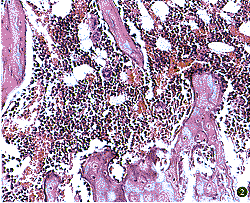

1.HE染色切片:(1)去势组股骨干骺端骨小梁明显变稀疏,皮质骨变薄,骨髓腔相对扩大 ,部分区域骨小梁消失,沿“S”形的骨小梁边缘有众多深浅不一的吸收陷窝,有些部分由于破骨细胞的溶骨作用,小梁出现中断(图2)。(2)对照组及治疗组股骨干骺端骨小梁丰富,皮质骨致密,小梁排列以纵向为主。在皮质骨形成表面4个治疗组均可见成队状排列似上皮细胞样覆盖于新生骨表面的成骨细胞,呈立方型、柱状和豆点状,有些细胞间有裂隙相连(图3)。

图2 骨小梁稀疏,骨髓腔相对扩大,部分区域骨小梁消失。HE染色 ×100

图4 骨小梁稀疏,表面骨吸收陷窝增多(↑)。甲苯胺蓝染色 ×100